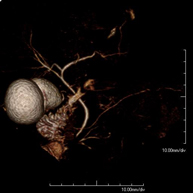

Prueba diagnóstica no invasiva que consiste en el estudio de la arteria aorta abdominal, obteniendo imágenes de alta definición anatómica mediante el empleo de un campo electromagnético y ondas de radio (con un emisor y un receptor). Es indispensable el uso de contraste paramagnético (Gadolinio). Sin embargo, no utiliza radiación ionizante. La calidad de las imágenes permite realizar reconstrucciones en 2D y 3D. Está indicado en aquellos pacientes con enfermedad vascular (aterosclerosis), estudio de aneurismas, en estudios pre-quirúrgicos de lesiones adyacentes a la aorta abdominal como "mapa" vascular, etc. - Angio RM Aorta-ilíaca

Prueba diagnóstica no invasiva que consiste en el estudio de la arteria aorta abdominal, obteniendo imágenes de alta definición anatómica mediante el empleo de un campo electromagnético y ondas de radio (con un emisor y un receptor). Es indispensable el uso de contraste intravenoso paramagnético (gadolinio). Sin embargo, no utiliza radiación ionizante. La calidad de las imágenes permite realizar reconstrucciones en 2D y 3D. Está indicado en aquellos pacientes con enfermedad vascular (aterosclerosis), estudio de aneurismas, en estudios pre-quirúrgicos de lesiones adyacentes a la aorta abdominal como "mapa" vascular… - Angio-RM Aorta iliaca